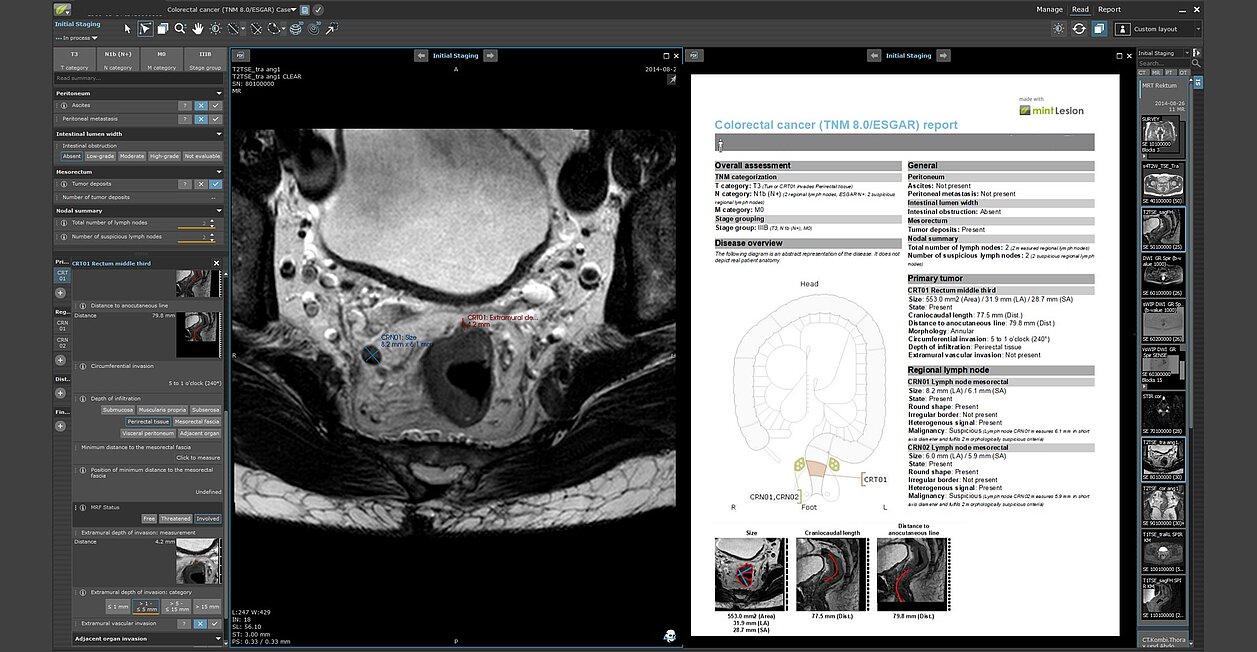

mint Lesion guides users through the reading process and ensures that all relevant information is collected in accordance with e.g. ACR-RADS classification, TNM guidelines or criteria for therapy assessment. It enables a clear and consistent documentation of the imaging information and significantly improves the completeness of the findings.